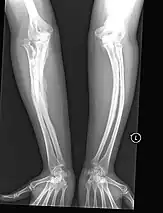

Left forearm

Right forearm

Right femur

Four X-rays of a 24-year-old American man, who had had more than one hundred bone fractures in his lifetime, and received a childhood clinical diagnosis of type IV–B OI. Genetic diagnosis in 2018 identified a previously uncatalogued pathogenic variant in the gene which encodes proα2(I) chains of type I procollagen, COL1A2, at exon 19, substitution c.974G>A. Due to childhood neglect and poverty, subject never received surgery to implant intramedullary rods. Malunions are evident as the humerus and femur were broken in adolescence but orthopedic care did not follow. Severe scoliosis, as well as kyphosis, are also evident. The unavoidably low contrast in the film is due to a combination of subject's obesity and low bone mineral density (BMD). Subject's BMD Z-score was -4.1 according to results of a dual-energy X-ray absorptiometry (DXA) scan also done in 2018.